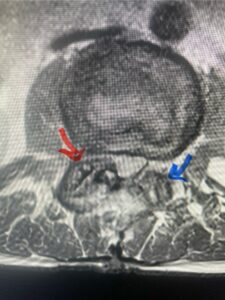

Figures 1a: Sagittal and axial T2-weighted lumbar MRIs demonstrating a grade 1 L2-3 spondylolisthesis (red arrow) with severe stenosis secondary to right L2-3 facet hypertrophy (red arrow).

Fig 1b: Note the left L2-3 facet joint (blue arrow) is normal in size compared to the right (red arrow)